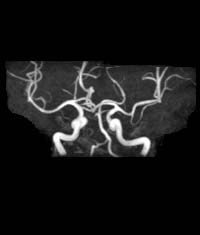

‰EFMRA

73Λ’jΊ

f’fF–«d–Œ‰ΊŒŒŽξ